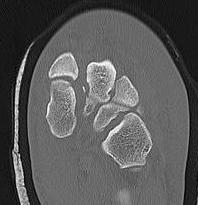

CT

Fleck sign